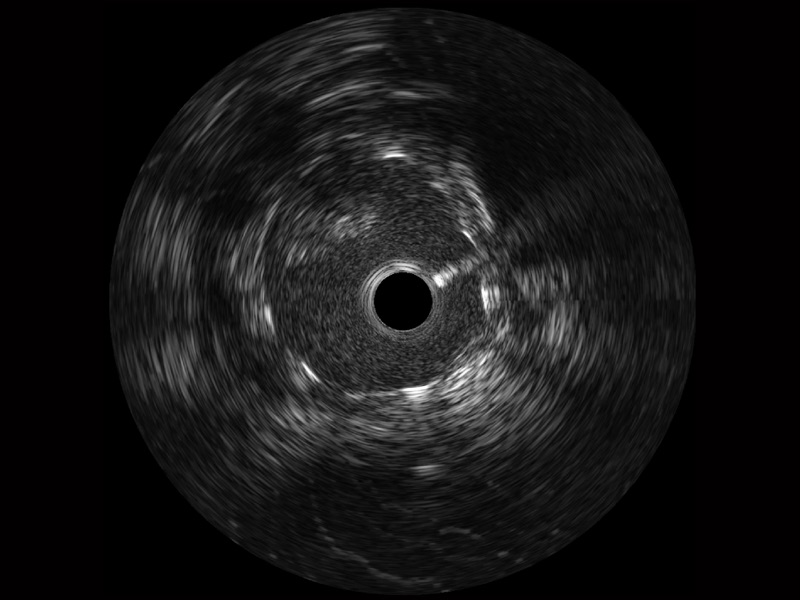

• 传统IVUS图像

对比传统IVUS导管成像,竞技宝(JJB)官方网站宽频IVUS图像的近场支架梁显影更细腻,远场中膜外血管仍清晰可辨,兼顾远中近,兼顾分辨力与穿透深度